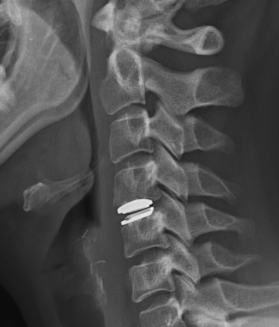

Disc replacement

Advantage

Theoretically maintain some motion and preserve other disc segments

Technique

Depuy Discover Medtronic Prestige

- anterior displacement

- posterior displacement and spinal cord injury

- subsidence 3% - higher risk if remove or disrupt end plates

- osteolysis

- implant failure

- heterotopic ossification